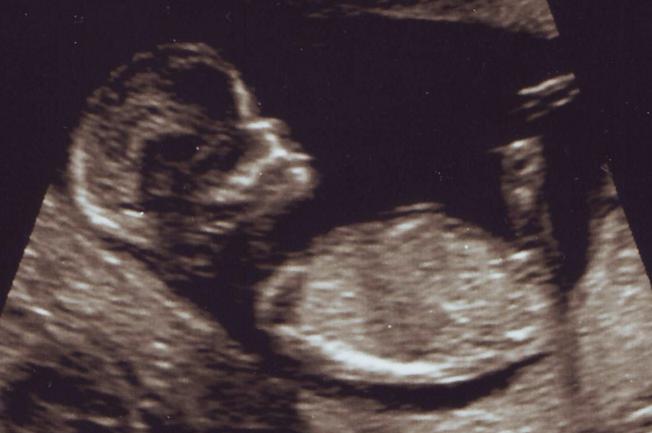

12w5d - Gentle Guesses Please!